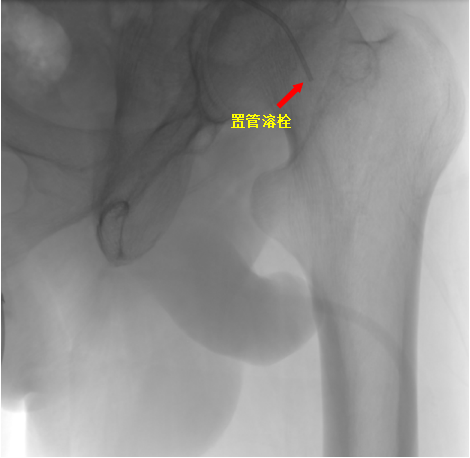

手术当天,易主任在病人左下肢动脉多处进行造影,考虑为血栓造成动脉闭塞,导管退至左侧髂外动脉起始部行溶栓治疗。